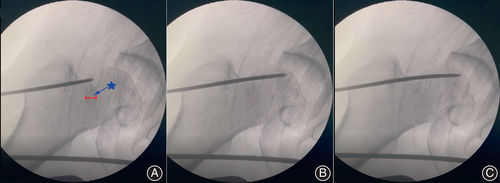

接下来,对残留的移位应用“内-外-内”经皮复位技术。在术中透视的帮助下,将带螺纹的斯氏针经皮钻入,通过股骨大粗隆上三分之一至股骨头。

在无股骨头后倾的外展嵌插型股骨颈骨折患者中,斯氏针的针尖将定位在股骨头中心;如果存在后倾,则斯氏针将从后方插入,向前倾斜至股骨头后部三分之一处。在透视下确认斯氏针的位置满意后,轻轻敲击针的末端,在透视监测下实现解剖复位。所有患者均通过经皮平行空心螺钉三角形配置固定。

首先,建议使用针尖带螺纹的斯氏针作为手术的复位工具。在达到理想位置后,螺纹斯氏针可提供更大的固定力来实现骨折的复位。

其次,斯氏针的位置取决于是否存在后倾。在无股骨头后倾的外翻嵌插型股骨颈骨折患者中,斯氏针的针尖应定位在股骨头的中心;如果存在后倾,斯氏针应从后方插入,向前倾斜至股骨头后部三分之一处。

最后,斯氏针应在透视监测下轻轻敲击,以防止穿透股骨头。第四,在骨折复位理想后,斯氏针应保持作为临时固定和定位针,直到经皮平行空心螺钉插入完成。